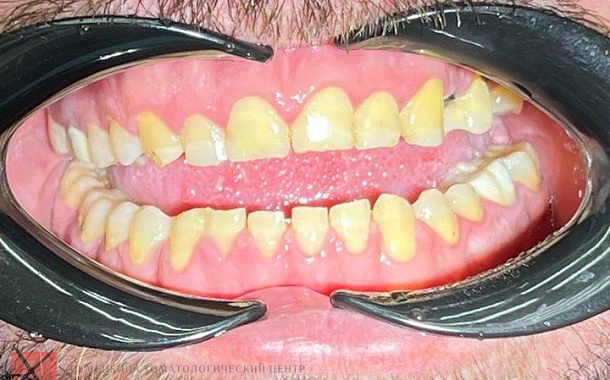

Полный прайс-листКейсы: до и после